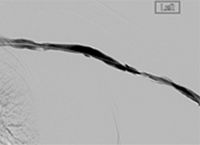

xray of occlusive thrombus extending into the iliac vein.

Occlusive thrombus extending into the iliac vein

xray of femoral vein pre-treatment.

Femoral vein pre-treatment